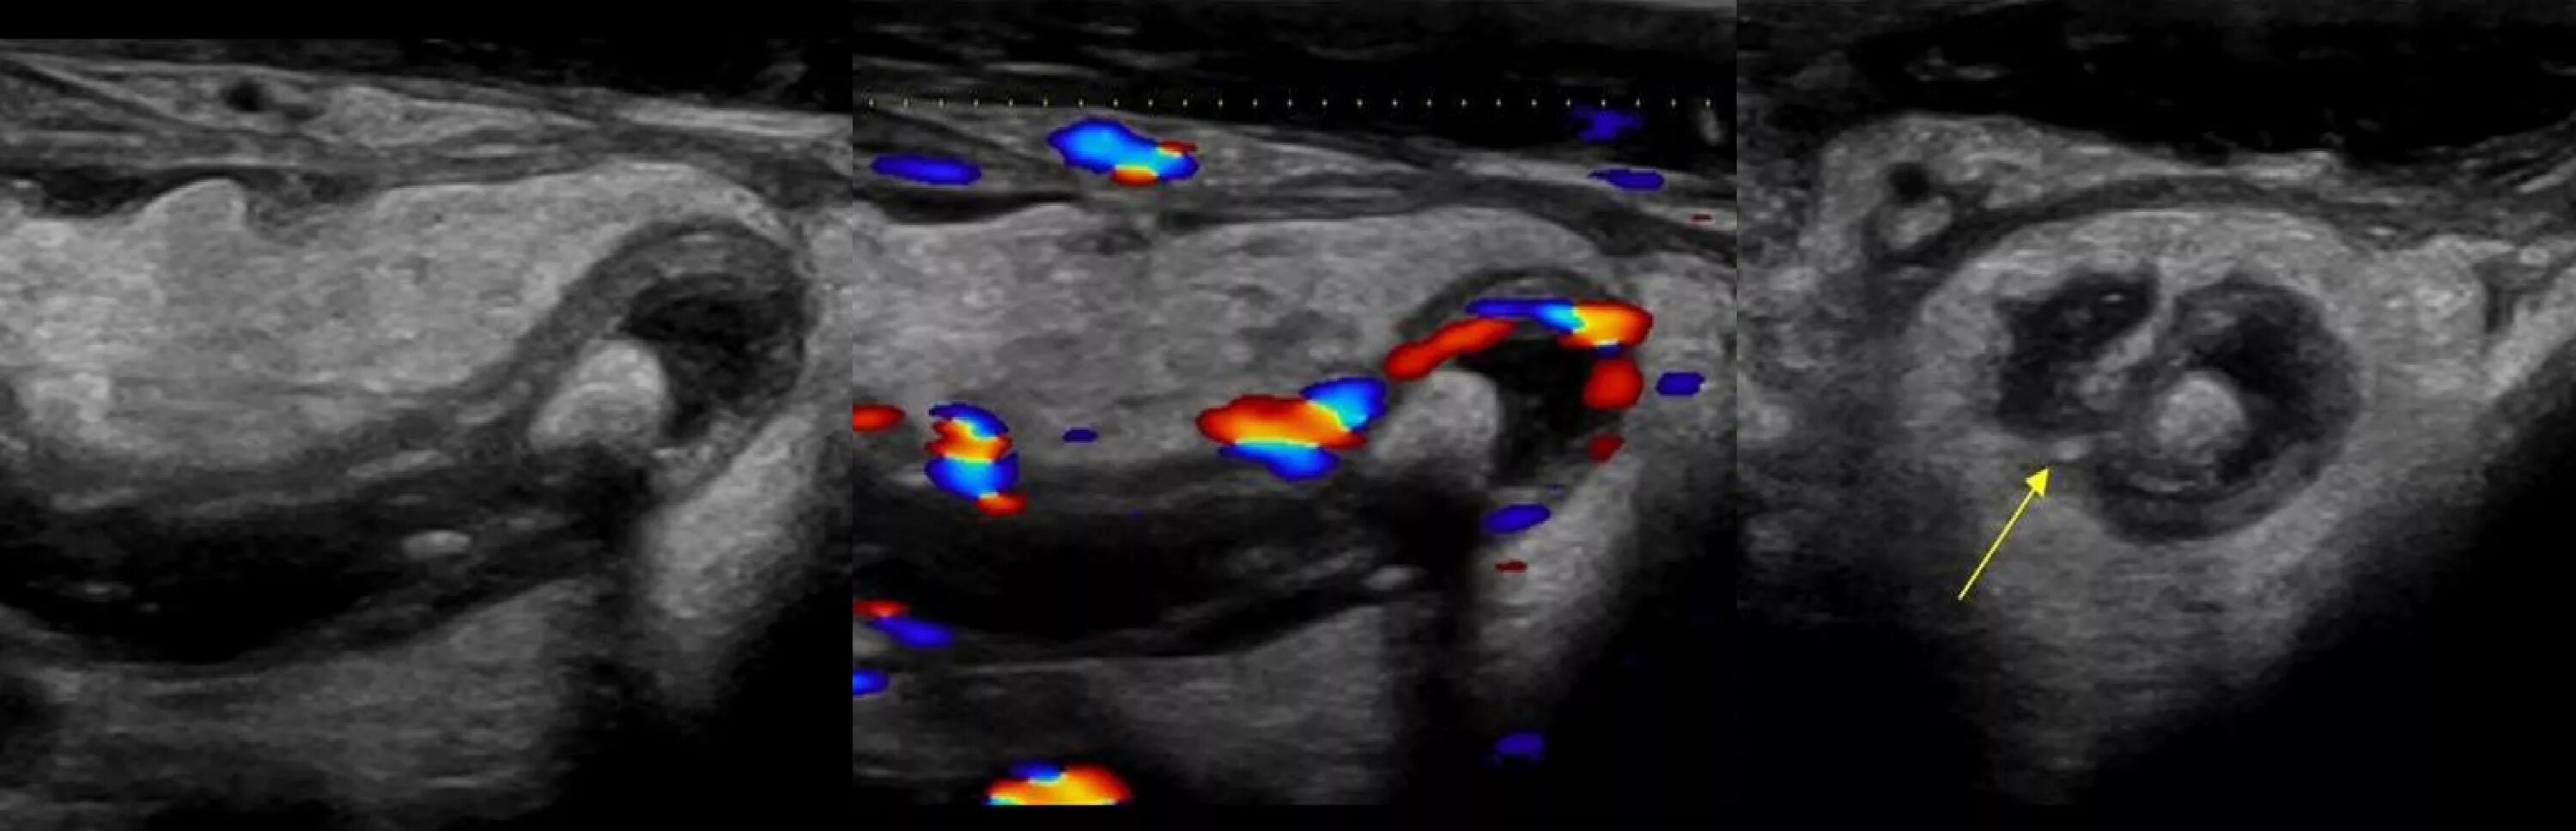

Аппендицит на узи можно ли